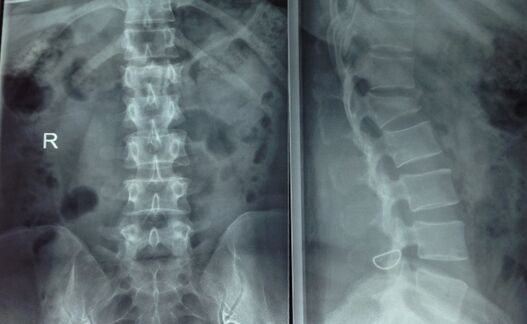

腰椎骨折

在家人的帮助下就医后,医生经X线检查、CT检查发现周老太出现腰椎骨折。据主治医生介绍,周老太之所以出现拥抱后骨折,是因为她有严重的骨质疏松。这导致她骨的脆性增加,稍微用点力甚至是在转身、打喷嚏、开窗等日常活动中,都有可能发生骨折。